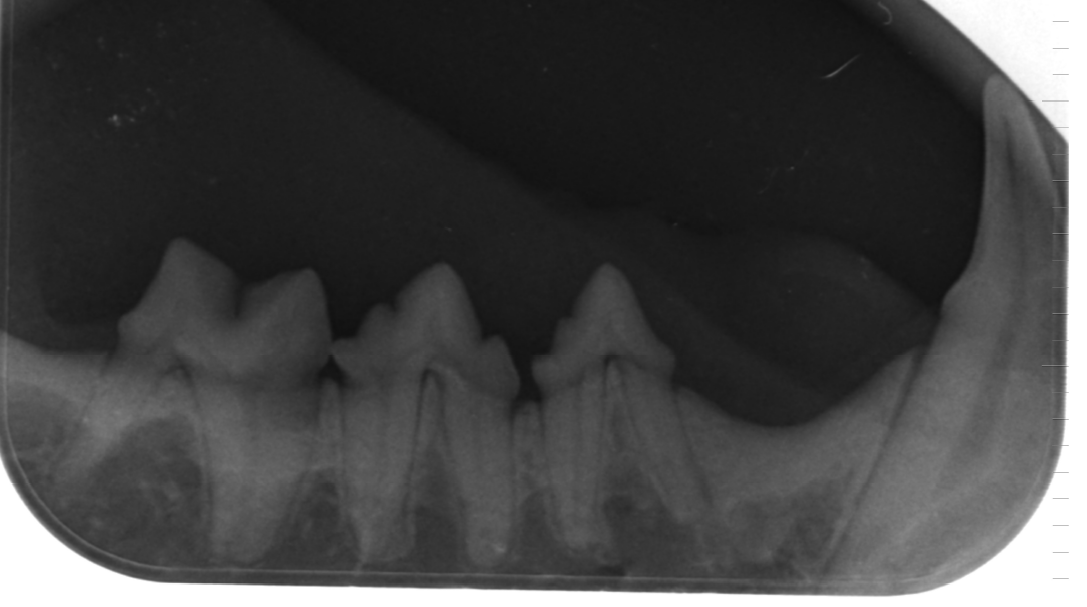

Zahnsanierung / Dentalröntgen

Zahnsteinentfernung per Ultraschall

Digitales Zahnröntgen.

Auch Zahnsanierung /Zahnkorrekturen von Heimtieren mit gut steuerbarer Inhalationsnarkose.

Seit 2001 sind wir für alle Zweifelsfälle auch mit einer digitalen Röntgeneinheit ausgestattet, die besonders feine Aufnahmen mit hoher Transparenz ermöglicht. Diese Röntgenbilder sind in Ihrer Aussagefähigkeit deutlich besser als normale Röntgenaufnahmen und ersparen damit häufig die Anfertigung einer Computertomographie. Herkömmliche Röntgenaufnahmen können bei uns ebenfalls durch Digitalisierung in die Datenverarbeitung genommen werden. In dieser Form sind sie als E-Mail versendbar. Seit 2019 haben wir auch eine digitale Zahnröntgeneinheit. Das erleichtert und beschleunigt die Zusammenarbeit mit beratenden Kollegen sowie die Informationsübermittlung bei Überweisungen auch über weite Distanzen.